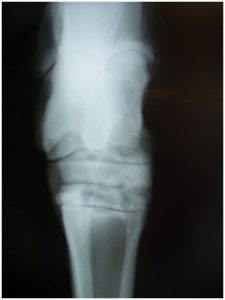

Digital Radiography

Waverly Equine Services has a top of the line portable digital x-ray system allowing for instant high-quality x-ray images. Digital radiography is one of several valuable diagnostic tools that allow an equine veterinarian to see changes inside your horse. X-rays are commonly used in diagnosing causes of lameness such as navicular disease, OCD, and osteoarthritis. They are also used to diagnose conditions such as tooth abscesses, sinus infections, kissing spine, cervical arthritis and much more. Radiography has been fundamental in equine diagnostic imaging for years and digital radiography takes it to another level.

The best thing for your horse is for the veterinarian and farrier to work closely together to try to determine how to keep your horse sound by providing the best foundation to help keep the foot and the rest of the body in balance. Often times what we see on the outsideof the hoof doesn’t tell the whole story and xrays can help determine how to better balance the foot.